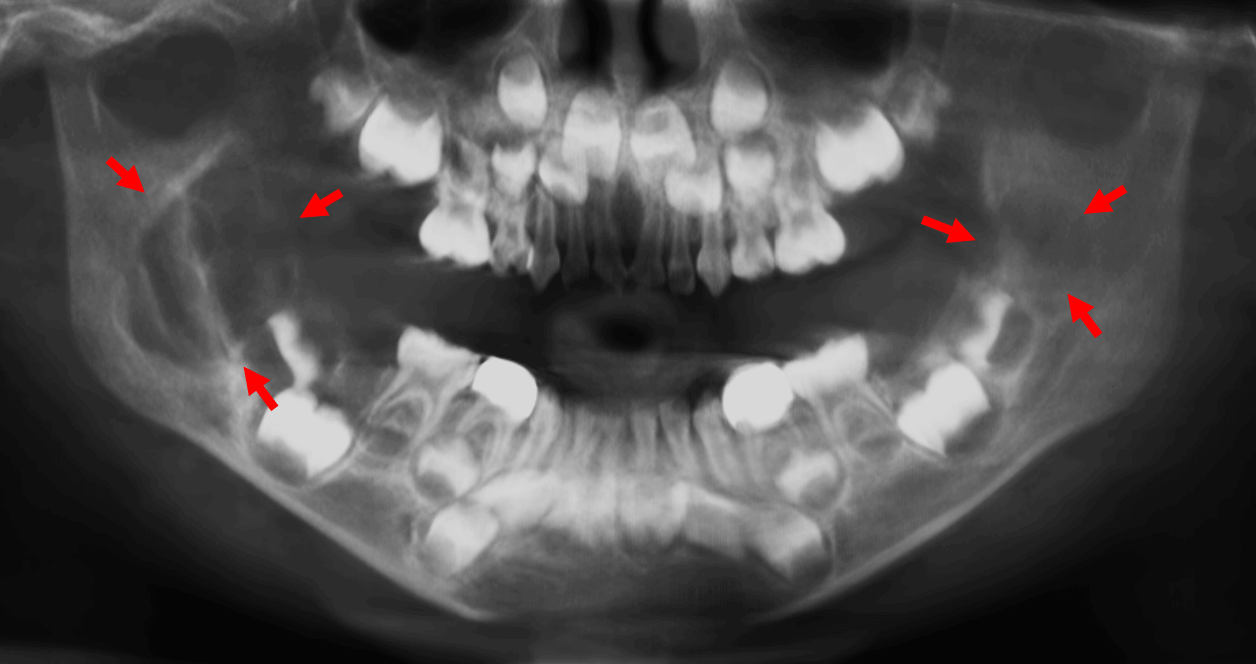

Fig.3

En el corte sagital del lado derecho (Fig.3) se observa la lesión osteolítica condiciona, la leve expansión, adelgazamiento y probable erosión de la cortical ósea del borde anterior de la rama ascendente (flechas rojas).

Fig.4

En el corte sagital del lado izquierdo (Fig.4) se observa también los mismos signos tomográficos del lado derecho, con la diferencia que de este lado la lesión es más pequeña, sin embargo, se encuentra en relación con el germen dentario del órgano dentario 47.